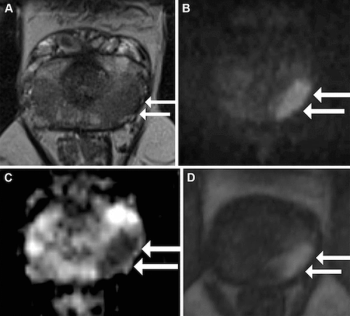

For men with prostate cancer, new research demonstrates that 18F-PSMA-1007 PET/CT is 17 percent more accurate than mpMRI at identifying the final pathological tumor stage and 12 percent more accurate in detecting extracapsular extension.